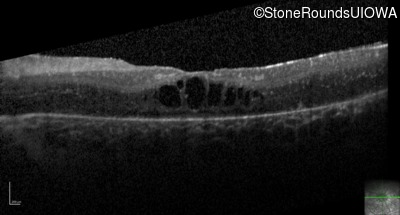

Optical Coherence Tomography - Right - 20/80 -1

Exemplar / OCT Stack

OCT Stack